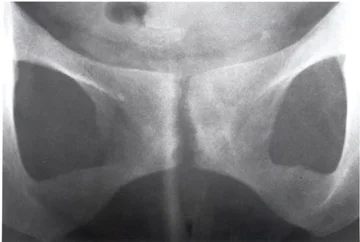

Osteitis pubis is a name covering several of the potential causes of chronic groin pain. In most cases, this condition can be treated successfully with physiotherapy. Read more...